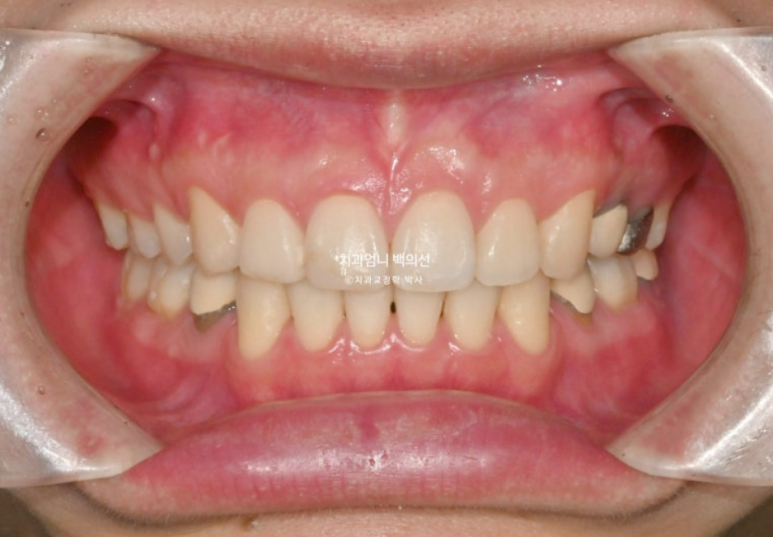

2022.12월 돌출입을 주소로 내원한 환자분 입니다.

앞니 중심선이 어긋나있고 앞니 기울어짐이 보입니다.

2022.12

앞니가 상당히 뻗쳐있는 상태 뻗침과 돌출이 심해서 입이 잘 안다물어지는 상태였고 골격분선상 골격성 2급 부정교합 (무턱)도 있습니다.